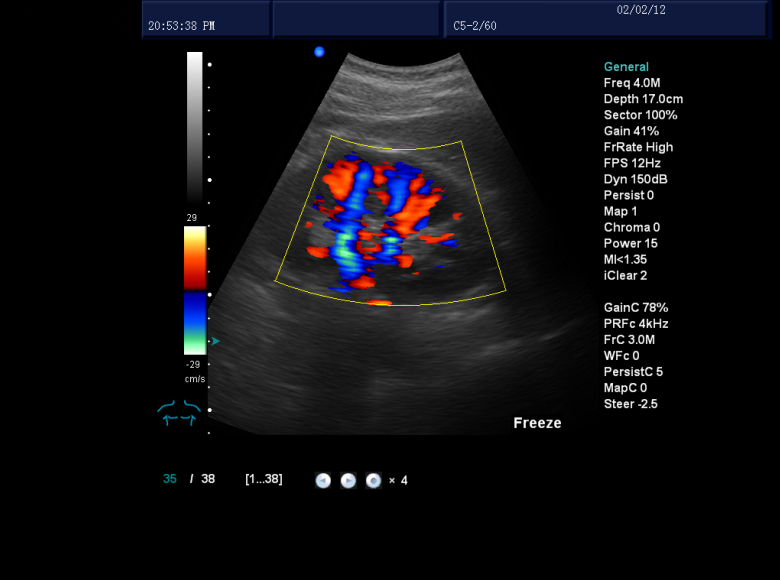

PL-6018II推車式彩超(獸用高清版)

品牌:派爾

型號(hào):PL-6018II

具備高精度數(shù)字化波束形成器——連續(xù)動(dòng)態(tài)聚焦、動(dòng)態(tài)可變孔徑、動(dòng)態(tài)濾波、動(dòng)態(tài)變跡,使得圖像真實(shí)、細(xì)節(jié)豐富。

具備數(shù)字化成像技術(shù)、標(biāo)準(zhǔn)PC平臺(tái)功能、專業(yè)設(shè)計(jì)控制面板,提升了臨床診斷需求系和統(tǒng)具備良好的可升級(jí)性。

具有高質(zhì)量的超聲圖像,廣泛適用于腹部、婦科、產(chǎn)科、泌尿科、血管、心臟、小器官及淺表等部位的檢查和診斷,同時(shí)也適用于計(jì)劃生育,即對(duì)早孕及節(jié)育環(huán)的檢查。

探頭:高密度、寬頻帶技術(shù),實(shí)現(xiàn)8段變頻功能,頻率范圍從2MHZ到12.0MHZ

動(dòng)態(tài)實(shí)時(shí)血管成像:通過精確的多普勒回聲信號(hào)自動(dòng)識(shí)別處理,減少血管壁和血流的多普勒信號(hào)回疊,使血管內(nèi)血液和血管多普勒成像顯示更清晰。

三同步顯示:二維、彩色和頻普三種模式同時(shí)處于實(shí)時(shí)狀態(tài),方便醫(yī)生對(duì)比觀察和定位取樣。 諧波成像:組織諧波成像使圖像更光滑、柔和、清晰,提升臨床診斷組織鑒別。